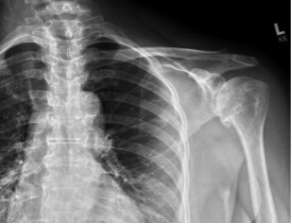

BH is a right hand dominant 70-year-old female, who is retired and moderately active. She presents with 8 months of progressively worsening left shoulder pain affecting her ADLS, sleep and recreational activities. She is 10 years s/p a right anatomic total shoulder arthroplasty. Radiographs and advanced imaging reveal glenohumeral joint advanced degenerative joint disease with an intact rotator cuff. Preoperative planning reveals a native 3 degrees of retroversion with 0 degrees of inclination. As she was extremely happy with the fully functional contralateral shoulder she has enjoyed for the past decade, she was interested in the same solution – an anatomic total shoulder arthroplasty.

At age 70 secondary rotator cuff tears following anatomic total shoulder arthroplasty must be weighed against complications and postoperative function of reverse shoulder arthroplasty [3]. Exactech Predict+ was able to demonstrate comparable postoperative function, scores, pain, and complications. A decision was reached to proceed successfully with an anatomic total shoulder arthroplasty.